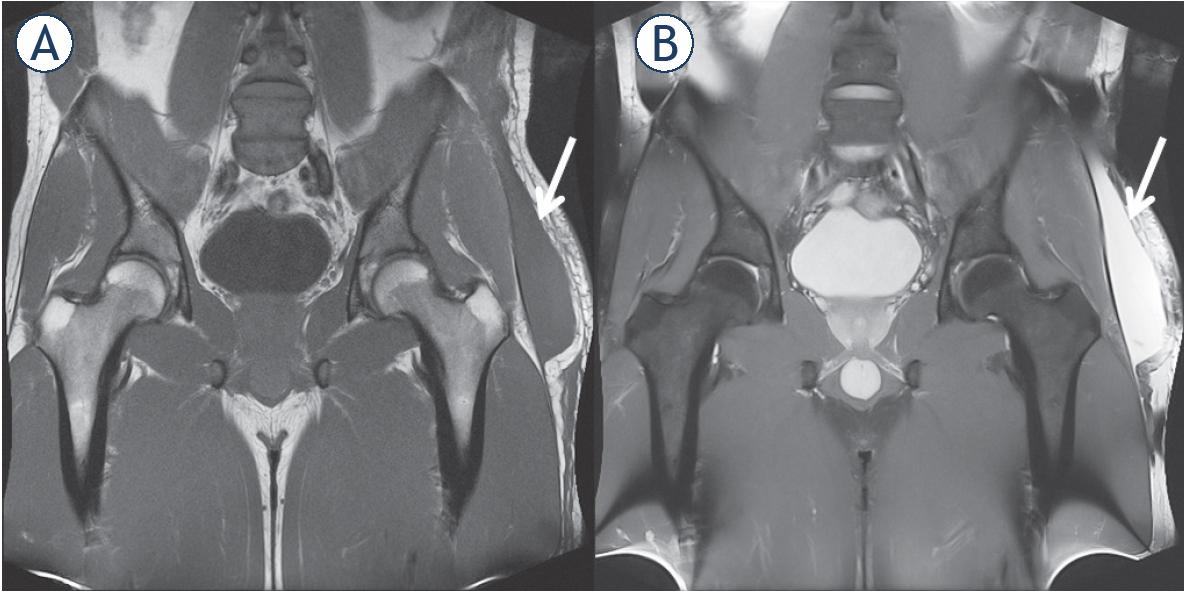

Figure 1